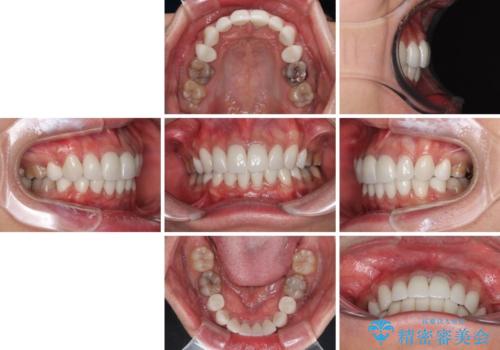

- 口元の突出感を改善するための抜歯矯正を終えた患者様ですが、幼少期からの変色した歯をセラミッククラウンにて自然な色合いに変えていくこととしました。

口を開けたときに目につく範囲を希望されたため上下ともに8本ずつをオールセラミッククラウンによる補綴治療を行うこととしました。

近年では大変珍しいですが、胎児あるいは乳幼児期の抗生物質の影響で永久歯が変色してしまうことがあります。

ホワイトニングでの改善は期待できないため、オールセラミッククラウンによる補綴治療が必要となります。